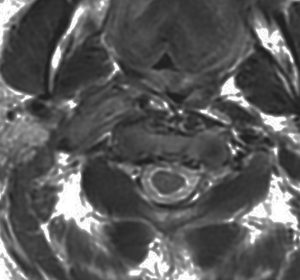

脊髄根 spinal rootから発生した無症候性の副神経鞘腫です。神経根は脊髄前根からでて脊髄の外側から背側へと上行するので,脊髄を横から圧迫するようになります。

徐々に増大しました。手術摘出を行うときに副神経を温存できないと,胸鎖乳突筋と僧帽筋の麻痺が生じます。